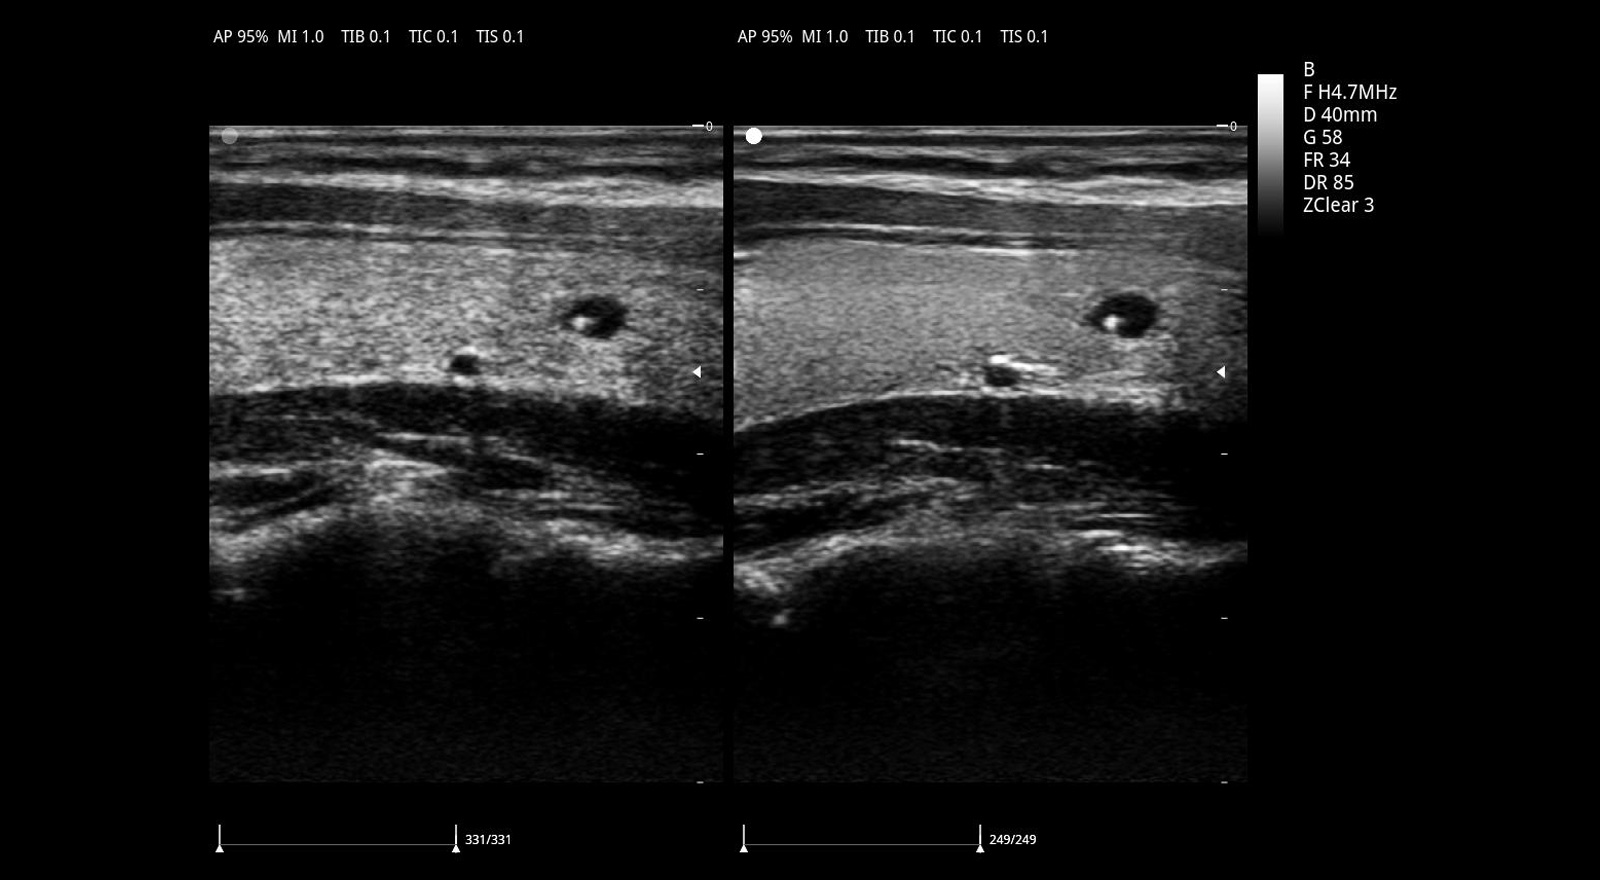

自适应空域滤波技术 zonClear

有效降低斑点噪声,大幅增强组织边界显示能力和组织回声显示能力